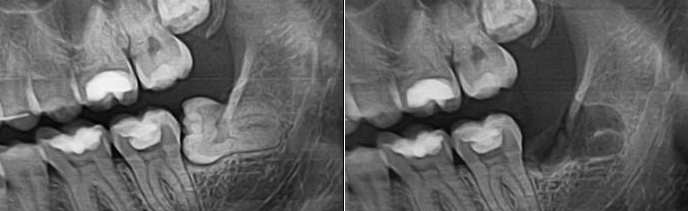

Удаление зуба мудрости: фото до и после

Эти зубы, как известно, появляются уже в зрелом возрасте. При этом они доставляют немало хлопот. Трудно режутся, вызывая высокую температуру, горячку, плохо, медленно и неправильно растут, мешают другим зубам, часто, только появившись, уже заражены кариесом или полуразрушены. Лечить такие зубы – дело неблагодарное и чрезвычайно сложное. «Восьмерки» - последние в ряду. Пациент не может как следует открыть рот, так чтобы у врача был хороший доступ к больному зубу. Каналы зубов мудрости часто длинные и искривленные, очень сложные для пломбирования. Словом, врачам не остается ничего, как заняться удалением 8го зуба. Есть и другие показания для операции. Например, он мешает впередистоящим зубам. Или неправильно наклонен. Или если он не может самостоятельно прорезаться. В этих случаях удаление верхнего зуба мудрости или того, что располагается снизу – не только показано, но и настоятельно рекомендуется.

Удаление ретинированного зуба мудрости (того, что не может самостоятельно прорезаться) или разрушенного – это уже более трудоемкая операция. Не говоря уже о том, что даже и в таких непростых случаях могут быть свои осложнения. Зуб может не просто плохо прорезываться, но и вдобавок расти под неправильным углом. В таком случае показано удаление ретинированного дистопированного зуба мудрости. Сложное удаление зуба мудрости, как правило, предполагает разрез в десне, извлечение зуба посредством высверливания, лечение и наложение швов. Реабилитационный период длится несколько дольше, есть определенные ограничения на диету и образ жизни. Возможны небольшие осложнения, вроде отека или подъема температуры тела, поэтому мы рекомендуем всем нашим пациентам, проходящим процедуру удаления зуба мудрости, взять больничный и посвятить несколько дней после операции восстановлению сил.